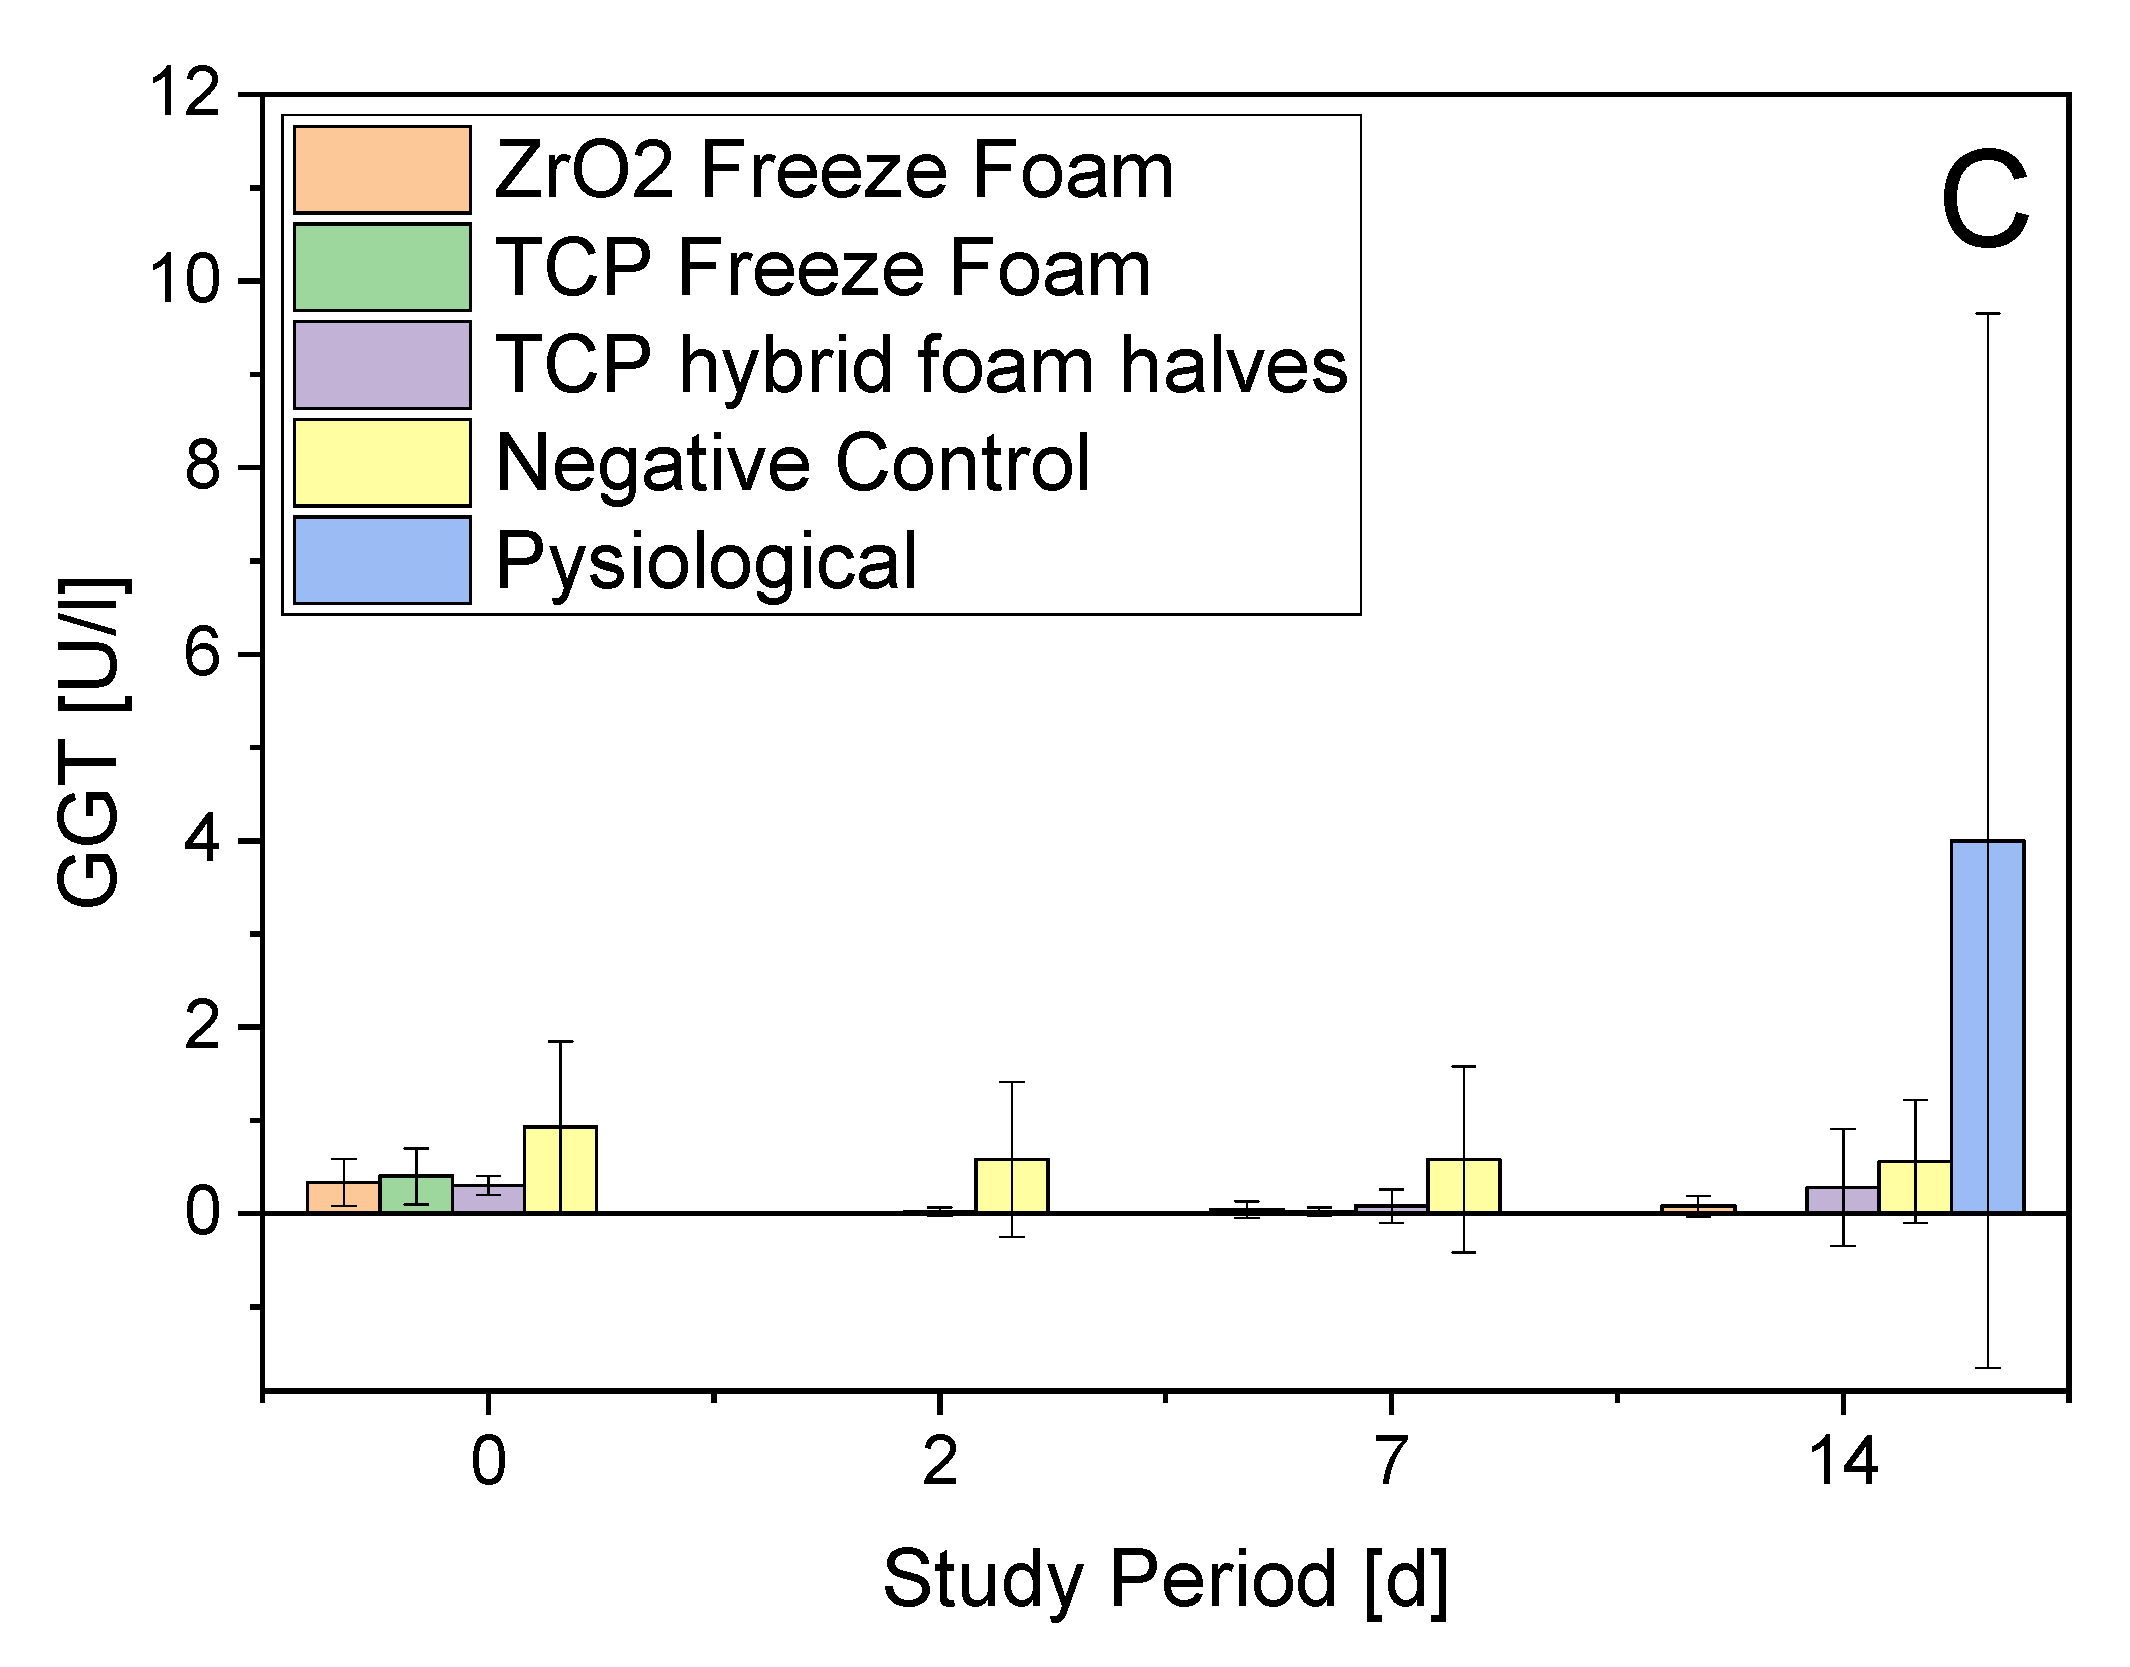

3.4. In Vivo Studies

- Serum Parameters

3.4.5. In Vivo Conclusion

4.2. Biocompatibility

5. Conclusions